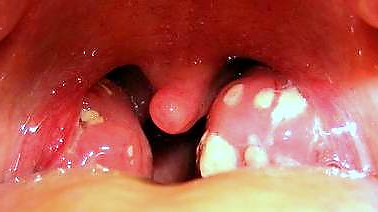

Síntomas de amigdalitis purulenta: causas, síntomas y ... 😈

Calaméo Amigdalitis 😈

¿QUÉ ES LA AMIGDALITIS? 😈

Síntomas de Amigdalitis: qué es, síntomas y tratamientos ... 😈

Que es la amigdalitis InMedicina.org 😈

Amigdalitis Aguda Dr. Jorge Treviño 😈

Amigdalitis en Niños: ¿Qué es? Causas, síntomas ... 😈

Amigdalitis: cuánto dura, qué síntomas tiene y más canalSALUD 😈